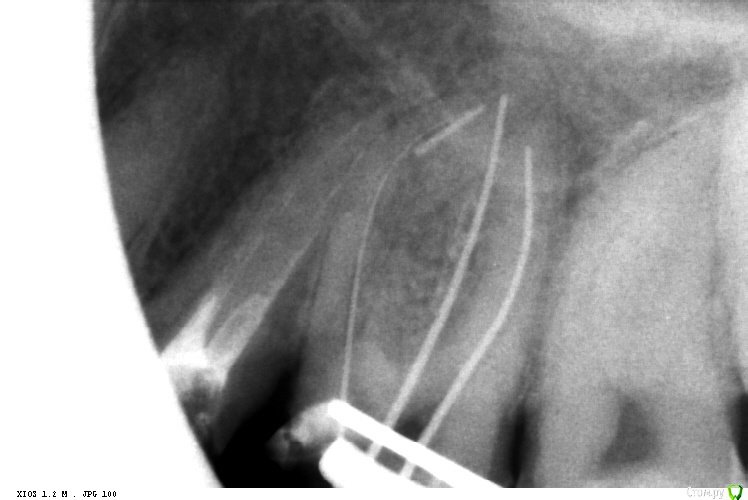

St. Опубликовано 29 октября, 2016 Автор Поделиться Опубликовано 29 октября, 2016 Реколл случая http://forum.stom.ru/topic/29857-endo/?p=529024. Прошло 11 месяцев после пломбировки)) 3 Ссылка на комментарий

Fred Опубликовано 29 октября, 2016 Поделиться Опубликовано 29 октября, 2016 Реколл случая http://forum.stom.ru/topic/29857-endo/?p=529024. Прошло 11 месяцев после пломбировки)) А почему такие жесточенные поры под реставрацией? Ссылка на комментарий

vse32 Опубликовано 29 октября, 2016 Поделиться Опубликовано 29 октября, 2016 А почему такие жесточенные поры под реставрацией? Может устья чем заливали, не контрастным. Свет, СИЦ? Ссылка на комментарий

St. Опубликовано 29 октября, 2016 Автор Поделиться Опубликовано 29 октября, 2016 (изменено) А почему такие жесточенные поры под реставрацией?Текучка градии нерентгенконтрастна. Как и сам материал большинства цветов. Керамика в планах. Ждали динамики. Изменено 29 октября, 2016 пользователем St. Ссылка на комментарий